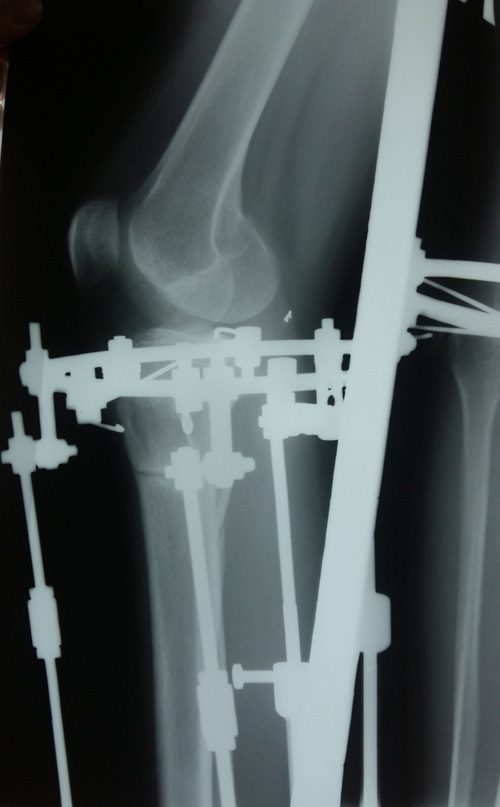

Рентген в 81 день с момента операции.

Здравствуйте, Соломея! По рентгену, у Вас всё отлично! В 90 дней возможно снятие аппаратов. Натаптывайте интенсивно ножки все эти дни, но без фанатизма(ведь когда я Вам говорю больше ходите- это значит, что при физ нагрузке быстрее разрастается костная ткань - вырабатывается, наступает сращение) лучше приехать и остаться у нас в клинике до снятия аппаратов. Один раз можно пожертвовать временем, расстоянием и средствами ради благополучия и отличного результата! Ножки мы исправляем один раз и навсегда!